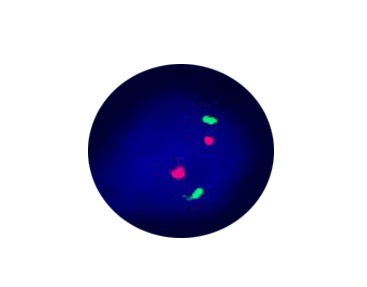

7q Segment Deletion

Probe Description: CUTL1 /7q35

Cat.No.: CF1128